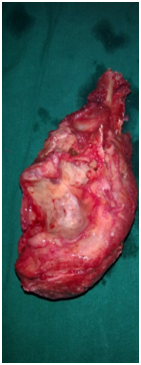

Under general anaesthesia tumour was exposed through posterior approach to elbow (Figure 3). Proximal ulna with tumour and 2cm of normal bone was excised (Figure 4). Another team of surgeons harvested required length of free fibular graft from upper fibula from ipsilateral leg. Head of the fibula was shaped to match the olecranon process of ulna and tensor fascia lata was covered over fibular head to act as articular surface (Figure 5). Graft was fixed to ulna using semi tubular plate and a K-wire was put for temporary immobilisation of elbow in 90degree flexion. Triceps tendon was sutured to the graft at proximal end. Specimen was sent for histopathological examination which confirmed the diagnosis of Osteoclastoma (Figure 6). Immediate post op X ray confirmed the proper fixation.

Figure 4 Excised tumour.